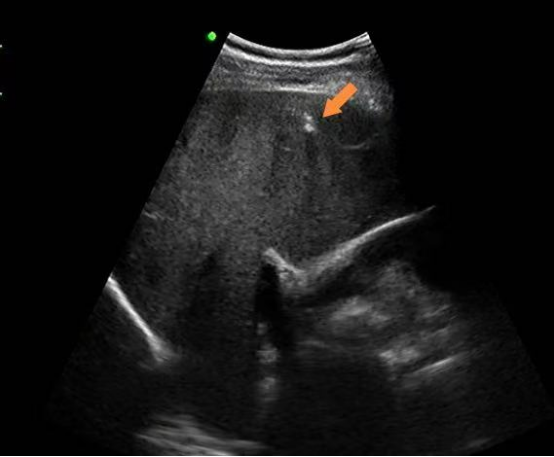

肝内钙化灶,简单说就是肝脏局部组织里的钙盐沉积。你可以把它想象成身体为了修复某个微小的肝脏损伤,而留下的一个"小补丁"。在B超或CT影像上,这些钙盐沉积会呈现为一个或多个白色的亮点。